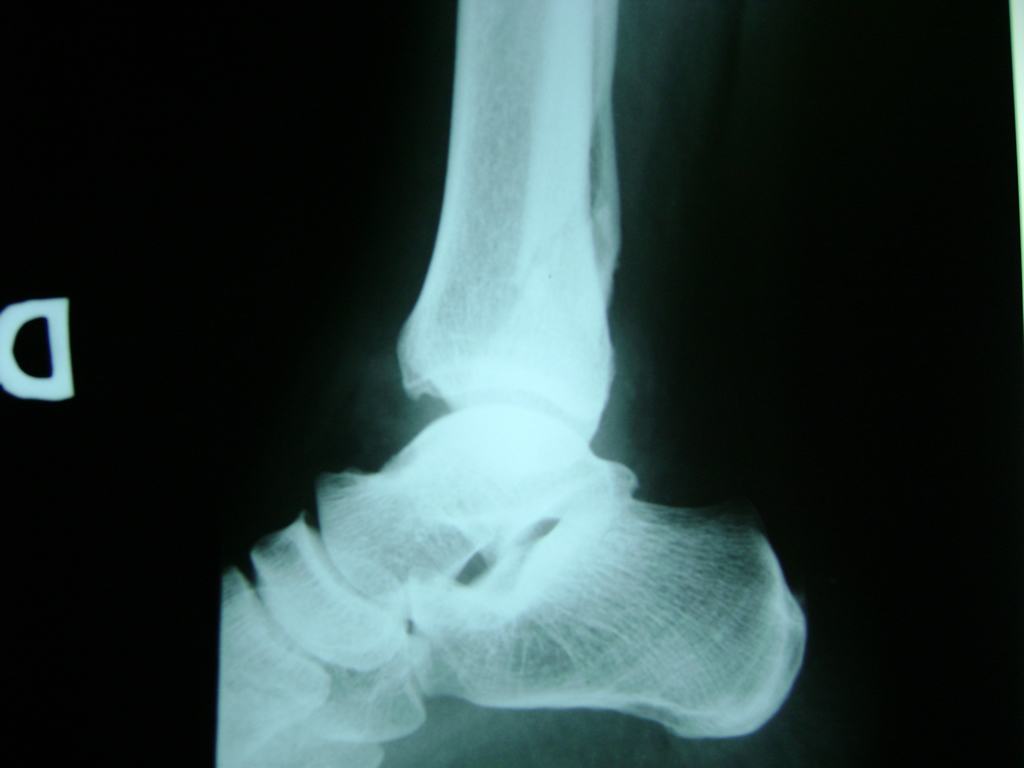

Una fractura de tobillo es la rotura de uno o más de los huesos del tobillo. Estas fracturas pueden ser:

- Parciales (el hueso está sólo parcialmente fisurado, no del todo).

- Los extremos de los huesos están desalineados entre sí (desplazados).